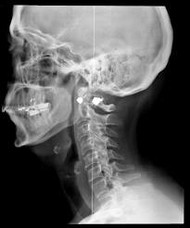

Astonishing new information about the damaging health effects of medical x-rays is the subject of a new book, Radiation from Medical Procedures, by John Gofman, M.D., Ph.D. Both a medical doctor and a nuclear physicist, Dr. Gofman is one of the world's leading experts in radiation damage. Dr. Gofman's evidence suggests that: Medical x-rays are responsible for an estimated 60 percent of all cancer deaths and 70 percent of all deaths from Ischemic Heart Disease (blockage of blood vessels).

For many years, studies have linked radiation exposure with most varieties of human cancers. Coming as a big surprise, Dr. Gofman's findings show that x-rays contribute to heart disease. What happens is this: x-rays cause mutations in the smooth muscle cells of the arteries, which makes the cells dystoreunctional and unable to process lipoproteins correctly. This in turn causes chronic inflammation of the arterial tissue, resulting in the accumulation of atherosclerotic plaque. This plaque eventually blocks the artery, resulting in heart attacks and strokes.

When one contemplates the implications of Dr. Gofman's conclusions, some alarming realities present themselves. First, medical radiation appears to be one of the principal causes of cancer and heart disease in America. Next, the amount of people who are affected is enormous. M.D.s order about 300 million xrays per year and dentists order another 100 million—perhaps helping to explain our increasing rates of cancer and other chronic diseases. Next, if one combines America's annual deaths from medical errors and prescription drugs (about 425,000) with the projected deaths from medical x-rays (about 750,000), this adds up to well over one million deaths per year being caused by our modern medical establishment. Thus, modern medicine would become the single largest cause of death in America.

Of course, diagnostic x-rays can be of benefit in certain situations, which is why they are still used—if overused. Dr. Gofman recommends that the total number of x-rays and the radiation dose of each be reduced. He believes that the number of x-rays could be cut by more than half without any loss of useful information. (Other researchers have estimated that up to 90 percent could be eliminated with no loss of useful data.) In addition, Dr. Gofman points out that x-rays are not the sole cause of cancer and heart disease. Rather, x-rays act as necessary co-factors in these diseases. That is, they are not the only factor involved in producing these diseases, but the disease will not happen without the x-ray.

If nothing else will get you to avoid x-rays, then consider this: X-rays bombard the atoms that make up your cells, "kicking" electrons out of their normal orbits and sending them flying at high speeds through your body's cells. These high-speed electrons crash into molecules that make up the genetic material in human cells and subject them to a uniquely violent kind of damage—mayhem that injures the genes so that they cannot be perfectly repaired (or even repaired at all). Put simply, exposure to x-rays can change the genetic coding of your cells, resulting in mutations that cause serious problems like cancer and heart disease. Do not expose yourself to x-rays unless absolutely necessary.